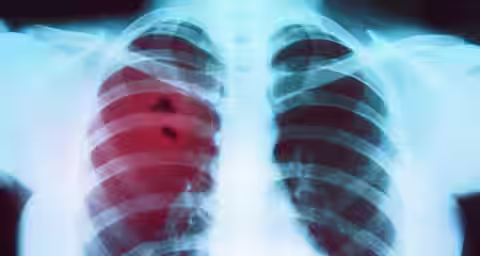

- Lung Cancer Misdiagnosis Cases

Lung Cancer Misdiagnosis Cases